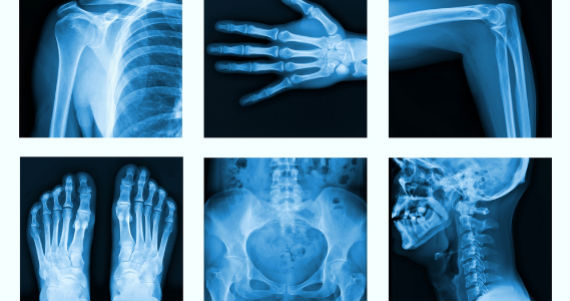

Según la encuesta de la Fundación internacional de Osteoporosis (IOF), a nivel mundial cada tres segundos se produce una fractura de hueso causada por esta afección, la cual afecta los huesos de quien la padece, y la Organización Mundial de la Salud (OMS) define como una densidad mineral ósea que es una desviación estándar de 2.5 o mayor por debajo del pico de masa ósea de jóvenes, adultos sanos, medidos con una densitometría ósea, es decir, una imagen de la cadera y de las vértebras necesaria para ver el grado de desgaste de los huesos y hacer un diagnóstico.